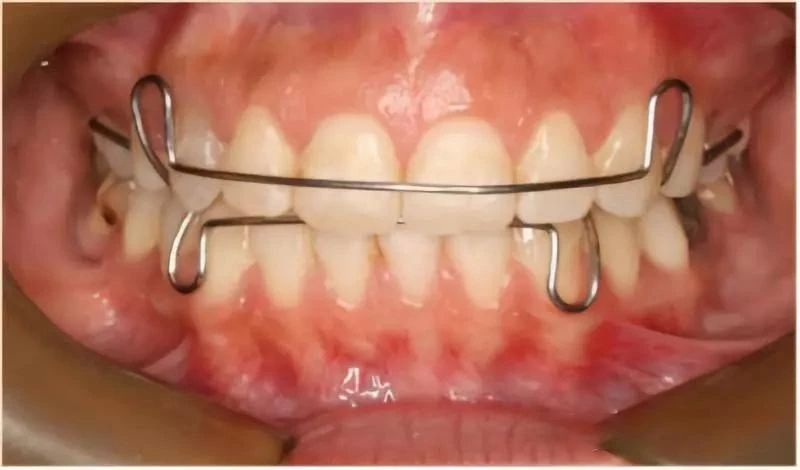

步骤六:调整牙齿定型

利用橡皮筋拉紧牙套,使牙缝收紧,调整牙套的位置,使牙齿达到整齐状态,要使牙套的中线和脸型对称。